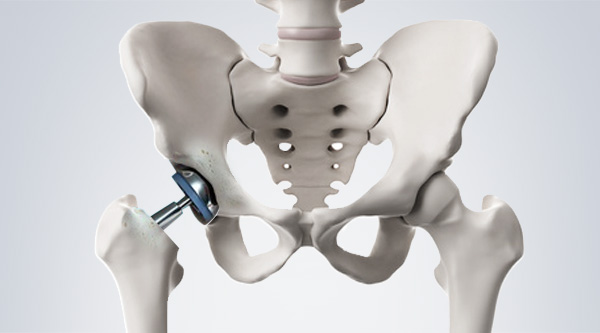

고관절은 엉덩이관절이라고도 불리우며, 보통 알고있는 골반위치에 있고, 공처럼 둥글게 생긴 대퇴골두가 글러브가 감싼듯한 모양으로 비구에 맞물려 있어요.

이렇듯 고관절은 오목하게 들어간 비구와 둥근 공모양의 대퇴골두로 이루어져 있으며 골반과 다리를 이어주는 우리 몸의 핵심 관절인데요. 그리고 고관절은 골반을 통해 전달되는 체중을 지탱해주고 걷기와 달리기같은 다리 운동들을 가능하게 해주는 관절이기도 해요.